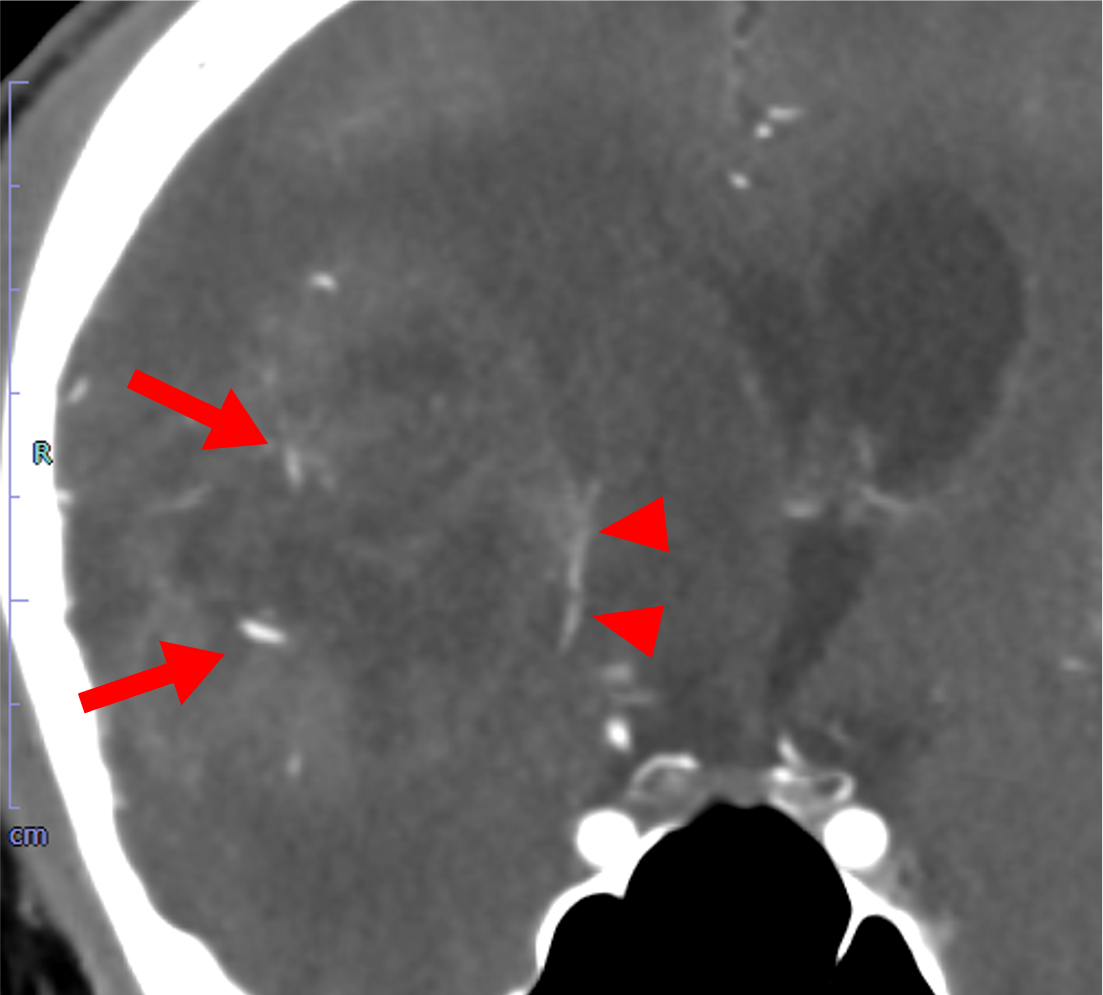

主訴は左下肢の脱力、歩行困難。右島回に5cm大の腫瘤を指摘され、膠芽腫が疑われた。術前の血管評価のため頭部CTA、CTVを施行した。

当該疾患の診断における造影CTの役割

島回部のglioblastomaの術前CTAにおいて、手術中の予期せぬ血管損傷の回避、ひいては術中出血や虚血性合併症のリスク低減のために中大脳動脈や穿通枝など主要血管を可視化する必要がある。血管と腫瘍の位置関係を把握することで、腫瘍をできる限り摘出しつつも神経機能を温存する戦略を立てることができるようになる。隣接する基底核部は錐体路や感覚路と近接するため、摘出範囲の判断のために術前の血管情報が不可欠である。

また、術前の血管画像をナビゲーションシステムに統合することで、リアルタイムに血管・神経の位置を確認しながら手術が進められ、より手術の安全性を高めることができる。膠芽腫は浸潤性が強いため、血管を温存しながらも腫瘍を完全に摘出することが困難であることが多く、機能温存と腫瘍制御の最適なバランスのために術前の詳細な血管描出が重要となる。

術前における頭部血管描出、特に細い穿通枝を十分に描出するため、動脈内のCT値を十分に上昇させることが不可欠であり、これはVR画像の作成においても重要な要素となる。そのため、なるべく高濃度のヨード造影剤を選択し、高容量を急速静注することが推奨される。さらに、生理食塩水で後押しを行うことでルート内や静脈内に残存した造影剤をフラッシュし、ボーラス性を高めることができる。加えて、低管電圧での撮影は血管内CT値の上昇に寄与し、描出能をさらに向上させる。

一方、頭部は静脈構造が複雑であるため、撮影タイミングが遅れると動脈の正確な評価が困難となる。したがって、脳静脈が描出される前に純粋な動脈相を取得することが極めて重要であり、造影される腫瘍病変と動脈を識別する上でも撮像のタイミングは大きな意味を持つ。実際の撮影ではボーラストラッキング法が簡便かつ汎用性の高い手法として多くの施設で用いられており、総頚動脈や中大脳動脈近位部でCT値をモニタリングし、一定の閾値を超えた時点で撮影を開始することが一般的である。画像処理に関しては、できる限り薄いスライスを用いることで評価の精度を高め、VR画像による立体的な血管走行の把握も重要となる。